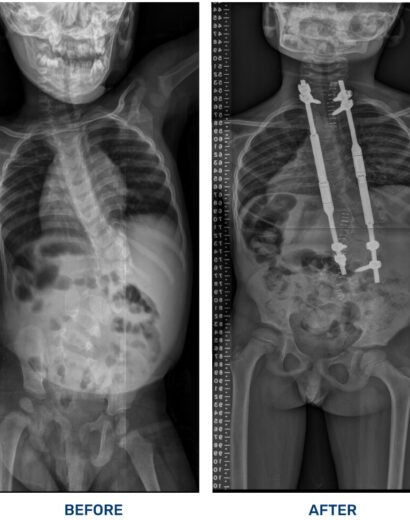

Success Stories

As Ghana’s leading orthopaedic and spine care hospital, we specialize in world-class treatments, cutting-edge surgeries, and personalized rehabilitation to help you move pain-free. Experience top-tier medical expertise, advanced diagnostic services, and patient-centered care in a state-of-the-art facility. Your health, our commitment.

FOCOS mission is to provide comprehensive, affordable orthopaedic care to those who would not otherwise have access to such treatment. Specifically, we strive to improve accessibility to top-notch surgical and non-surgical care for patients who suffer from debilitating musculoskeletal conditions, such as complex spine deformities and pediatric orthopedic problems, in underserved areas. It all began as a dream of the founder to see the best care reach the underserved in his native country, Ghana and the sub-Saharan region.